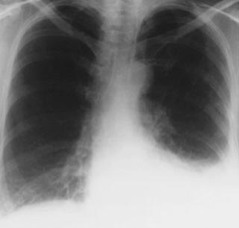

Derrame pleural

-Efecto directo del páncreas

-Paso del liquido a través de defectos diafragmaticos

*liquido pleural con grandes cantidades de proteínas, lactato deshidrogenasa y amilasa*

Complicaciones pulmonares

-Aumento de la permeabilidad de membrana alveolocapilar

-Destrucción de células endoteliales en capilares alveolares

-Destrucción del surfactante

-Inflamación del tejido